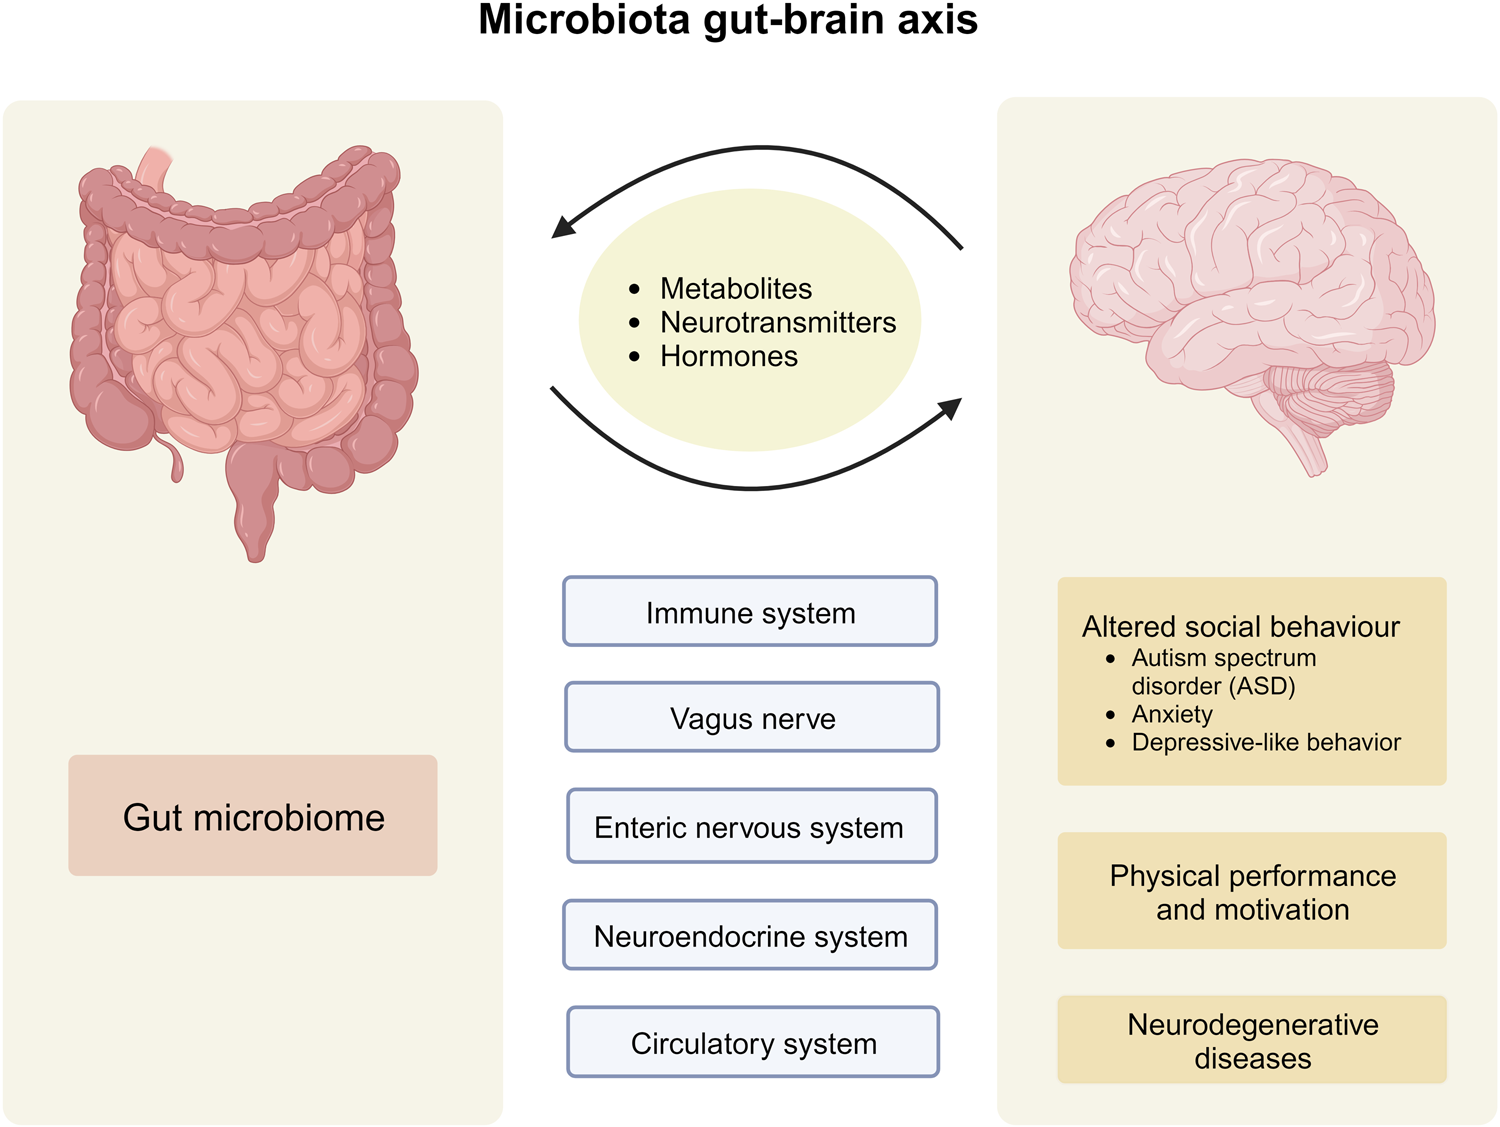

The human gut microbiome is a complex ecosystem that both affects and is affected by its host status. Zhavoronkov says this “microbiome aging clock” could be used as a baseline to test how fast or slow a person’s gut is aging

Previous analyses of gut microflora revealed associations between specific microbes and host health and disease status, genotype and diet.